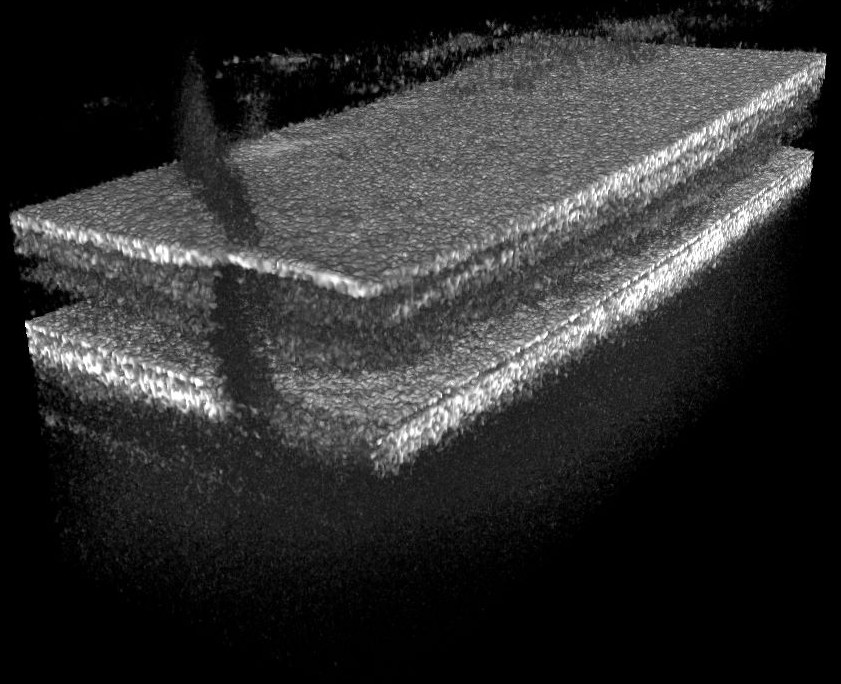

Holoscopy applies refocusing techniques to the full-field OCT signals, restoring lateral resolution over tens of Rayleigh lengths. Combined with an off-axis reference wave maximal use of the coherence length of the swept laser source can be made, if reconstruction is only applied to the signal term. Fig. 7 shows a scattering sample of polyurethane resin doped with iron-oxide nanoparticles of sizes between and [24], where the signal term over positive and negative path lengths was successfully refocused. By using a numerical reconstruction technique for holoscopy [17, 18] backscattered light was detected with almost optimal lateral resolution in the full-range images over a depth of more than .

Imaging the whole eye with FF-SS-OCT or holoscopy suffers from strong reflections at the different optical interfaces of the eye, which we expect to introduce significant autocorrelation noise or an increased noise floor when being incoherent with respect to the sample light. With off-axis recording and filtering of non-signal terms a complete ex vivo porcine eye, with both anterior and posterior segment, i.e. retina, lens, and cornea was imaged in a single data set (Fig. 8). The sweep range of the light source was reduced to , sacrificing resolution for a total measurement depth of more than when sampling the sweep with 2048 data points. By numerical refocusing on the signal term both retina and cornea were reconstructed sharply. To reduce noise, we acquired and averaged 9 volume data sets. Reflection induced artifacts and remaining DC signals were identified by their constant phase values in all images and removed numerically.